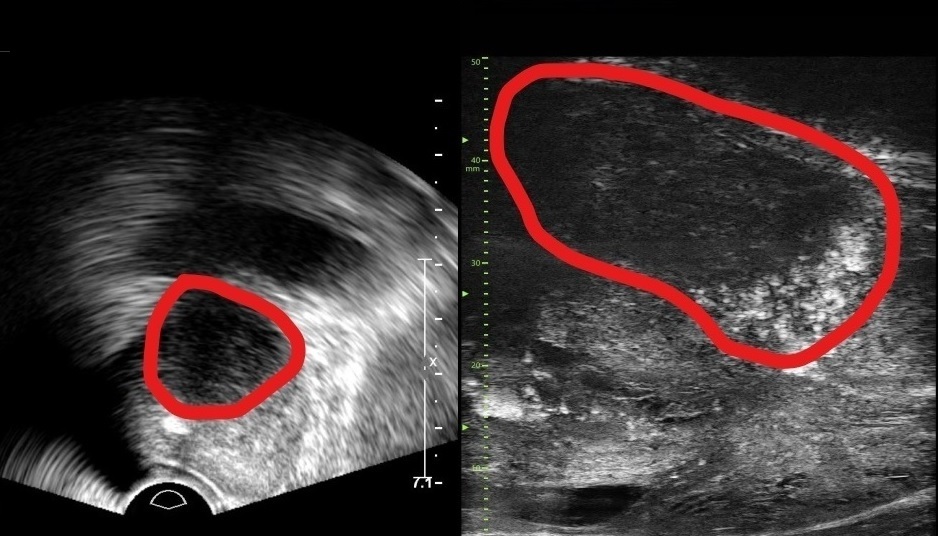

• 해상도 3배 높인 ‘마이크로 초음파’ 최초 도입

분당서울대병원 비뇨의학과가 기존 초음파보다 해상도가 약 3배 높은 실시간 영상으로 전립선 종양을 평가할 수 있는 ‘마이크로 초음파’ 장비를 국내 최초로 도입했다. 이번에 도입된 장비는 29MHz 마이크로 초음파를 사용해 전립선과 주변 구조를 기존보다 훨씬 더 선명하게 보여준다. 이를 통해 의심 부위를 실시간으로 파악하고, 병변의 미세한 변화를 확인하면서 조직검사 바늘을 정확한 위치에 삽입할 수 있는 것이 큰 장점이다.마이크로 초음파는 전립선암 진단 가이드인 PRI-MUS 위험도 식별 시스템과도 연동된다. PRI-MUS는 초음파 영상